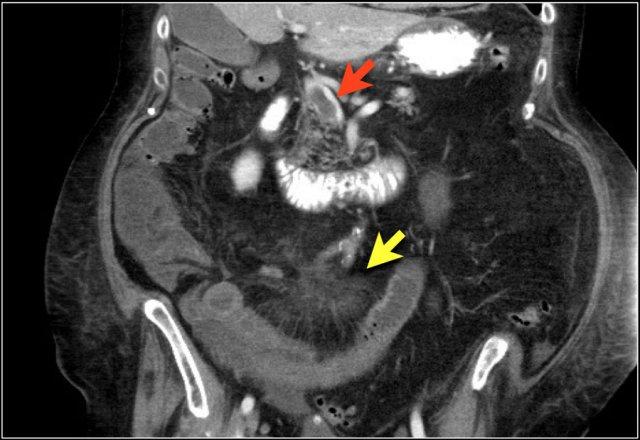

Đây là một bệnh nhân khác bị thiếu máu cục bộ một đoạn dài ruột non do tắc ruột quai kín.

Một đặc điểm hình ảnh quan trọng của tắc ruột quai kín là hình ảnh các quai ruột non giãn xếp theo kiểu nan hoa bánh xe với các mạch máu mạc treo hội tụ về một điểm trung tâm.

Các dấu hiệu thiếu máu cục bộ trong tắc ruột quai kín tương tự như ở các bệnh nhân có nguyên nhân thiếu máu cục bộ mạc treo khác:

- Dày thành ruột

- Phù nề mạc treo ruột

- Cổ trướng

- Sự ngấm thuốc của thành ruột trong thiếu máu cục bộ có thể bình thường, tăng do hiện tượng tái tưới máu, hoặc giảm/mất ngấm thuốc như trong trường hợp này.